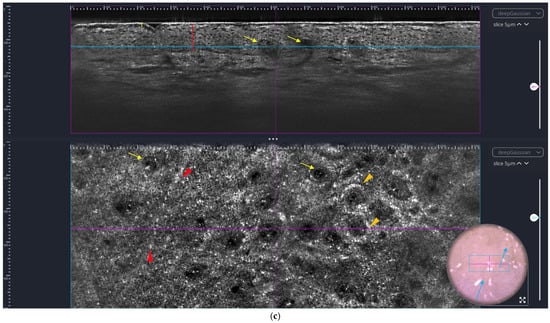

One of the most intriguing findings in our study was the long-term persistence of elongated vessels, sometimes showing a psoriatic vasculature in the CoA. For better understanding, a review of the vessels within the 3D stacks was carried out, depicting the vessels better by applying minimal rendering to the LC-OCT scans, demonstrating a longer persistence under therapy than other dermo-epidermal alterations (see Figure 10). The segmentation of the vessels was still carried out manually when needed and still highly time-consuming. The training of an AI model this could be realized more rapidly in the future.

Figure 10.

Depiction of vessels at V0 (‘Before’) and V2 (‘After’ 12 weeks of therapy) via line-field confocal optical coherence tomography (deepLiveTM, Paris, France) (upper image part of vertical and horizontal view (vertical image size: LC-OCT image size: 1.2 mm × 0.4 mm; horizontal image size: 1.2 mm × 0.5 mm), blue line corresponding to the height of the depicted horizontal image within the 3D stack, purple line corresponding to the location of the depicted vertical image within the 3D stack, accompanying dermoscopy picture (image size: 1.2 mm × 0.5 mm), bottom minimal rendering of 3D block for better visualization of vessels (3D image size: 1.2 × 0.5 × 0.5 mm3)). Initially, there were highly increased vasculature and typical glomerular vessels in elongated rete ridges; after 12 weeks of therapy, despite clinical remission there is a persistence of augmented vascularization; and now, more reticular vessels can be seen but the ends of the vessels still have a glomerular aspect (for a video animation of the vasculature, please see S1 and S2 in the Supplementary Section).